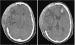

Mediainfarkt und Kraniektomie. Derzeitige Studienlage, Operationsindikationen und organisatorische Aspekte Journal für Neurologie, Neurochirurgie und Psychiatrie 2008; 9 (4): 12-19 Volltext (PDF) Summary Praxisrelevanz Abbildungen Keywords: Kraniektomie, Mediainfarkt, Neurochirurgie Vor dem Hintergrund der derzeitigen Studienlage ist es erforderlich, an neurochirurgischen Abteilungen die dekompressive Hemikraniektomie für eine bestimmte Gruppe von Schlaganfallpatienten anzubieten. Bei Patienten mit ausgedehnten, akut raumfordernden, so genannten "malignen" Mediainfarkten konnte die unter konservativer Behandlung bei bis zu 80 % liegende Mortalität durch dekompressive Hemikraniektomie auf < 30 % gesenkt werden. Über 40 % der so operierten Patienten erlangten in weiterer Folge wieder funktionelle Unabhängigkeit. Die vorliegenden Daten bestätigen, dass Überleben und gutes neurologisches Outcome nach Mediainfarkt und Kraniektomie vor allem dann zu erwarten sind, wenn jüngere Patienten (< 60 a) unabhängig von der Seite des Infarkts früh (< 48 h nach Symptombeginn, zumindest aber vor Manifestation neurologischer Zeichen der Hirnstammkompression) zur Operation gelangen. Der Harmonisierung der organisatorischen Abläufe im Vorfeld der Operation sowie der postoperativen intensivmedizinischen Betreuung und neurologischen Rehabilitationkommt besondere Bedeutung zu. |